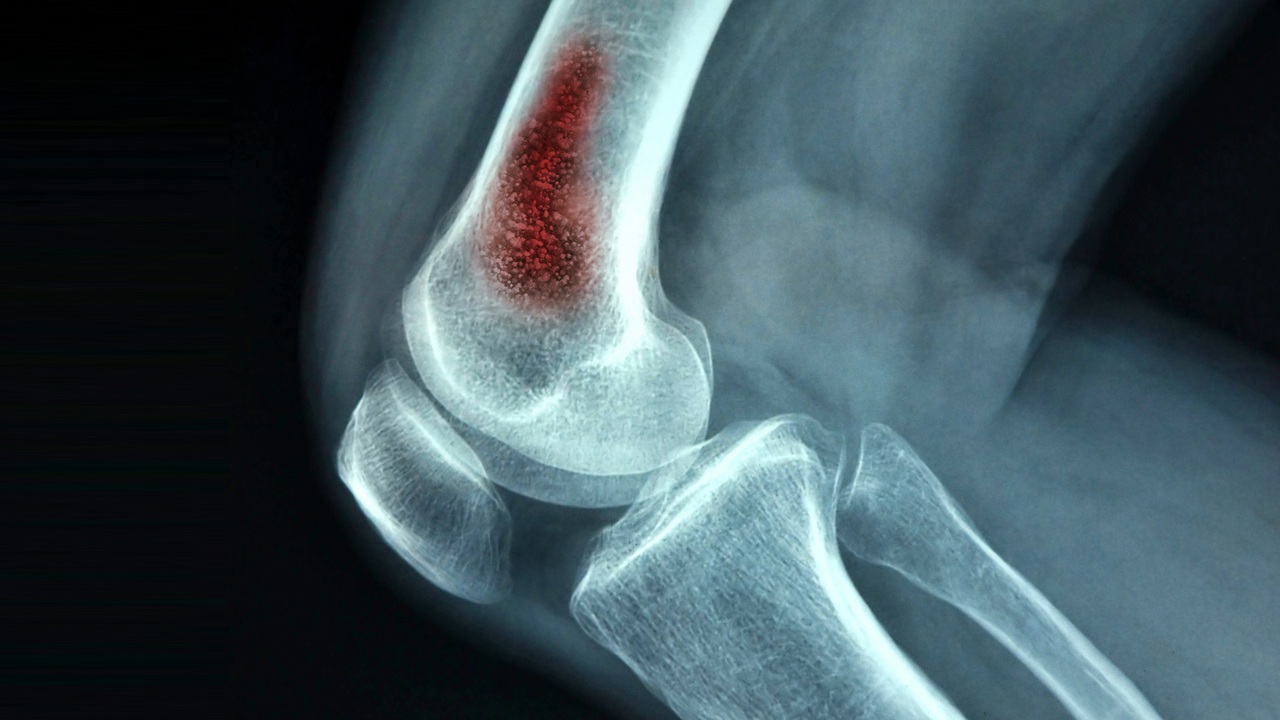

عفونت استخوان یا استئومیلیت چیست؟

به زبان ساده عفونت در استخوان، به معنی نفوذ باکتری به بافت و مغز استخوان و آلوده کردن استخوان است. به عفونی شدن استخوان، التهاب استخوان نیز گفته میشود که جزو موارد پزشکی خطرناک است و باید فوراً درمان شود؛ زیرا آسیبهایی که عفونت به استخوان وارد میکند، جبران ناپذیر هستند. چندین دلیل وجود دارد که باعث میشوند استخوان عفونت پیدا کند که یکی از آنها، شکستگی استخوان است.